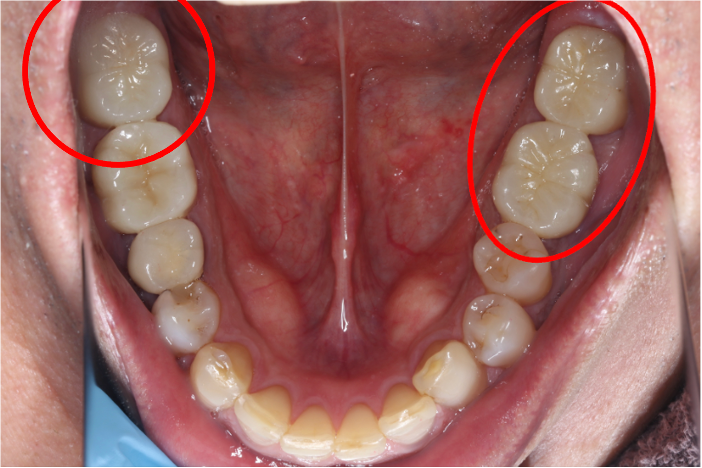

セラミック症例①

年齢40代女性

治療期間1ヶ月

治療内容ジルコニア、セラミックインレー、セラミッククラウン

治療箇所左上1番、2番 左下5番、7番 右上1番、2番、3番、4番、5番 右下5番、6番、7番

治療費用100,000円